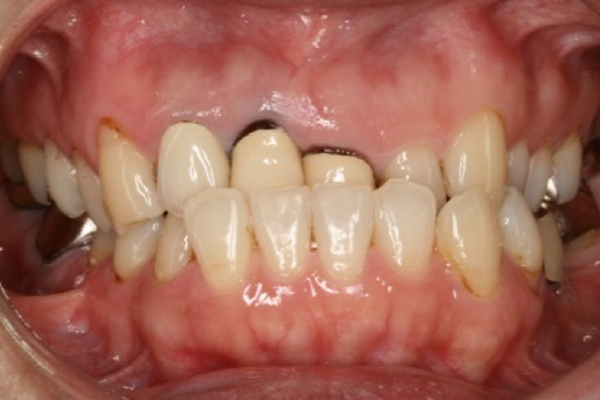

受け口の治療前

上の写真のように、以前であれば外科矯正を行ったようなケースでも、今はインプラント矯正によって、受け口(下顎前突)や、オトガイ部の突出感も改善できることがあります。

①受け口(下顎前突)の矯正治療例(50代女性・治療期間2年2か月)

| 年齢・性別 | 50代女性 |

| 治療期間 | 2年2か月 |

| 抜歯 | なし |

| 治療費 | 100万円(調整費、保定費まで含む総額制) |

| 備考 | 裏側矯正、QH拡大、歯冠長延長術、補綴物再作製 |

| リスク・副作用 | 痛み・治療後の後戻り・歯根吸収・歯髄壊死・歯肉退縮 |